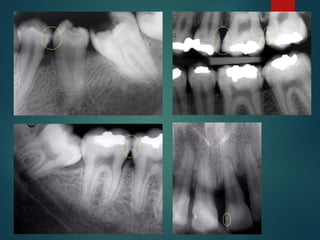

Diagnostico Radiografico de Caries

 Alrededor del 30% de las caries existentes no

pueden verse sin control radiográfico

 Las radiografías de aleta de mordida son las más

adecuadas para descubrir estados precoces de

la caries

La caries es detectable

radiográficamente por que

produce una desmineralización del

diente, esta zona permite un paso

mayor de Rayos X que impresionan

la película